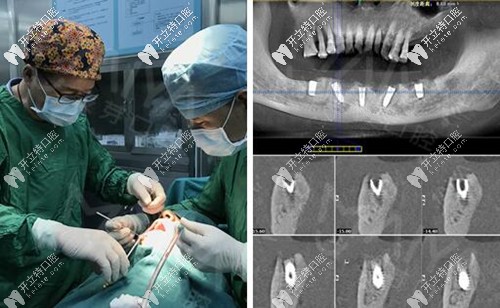

麥芽口腔的種植牙博士看過我的片子后,說我的下半口牙槽骨萎縮厲害,現(xiàn)存的骨量不適合做傳統(tǒng)的滿口種植牙手術(shù),因此給我設(shè)計(jì)了“all-on-4”種牙技術(shù)的升級(jí)版本“all-on-5”,也就是說恢復(fù)半口牙齒需要種5顆植體,安裝上“架橋式”的牙冠就可以了。

其實(shí),做種植牙根本沒有自己想象的疼,打完麻藥不到5分鐘就起作用了,半口種植牙的5顆牙釘不到一個(gè)小時(shí)就種完了,感覺自己就瞇了一會(huì)就好了。牙釘種好之后,戴的是臨時(shí)牙冠,不過當(dāng)天就能吃東西~~